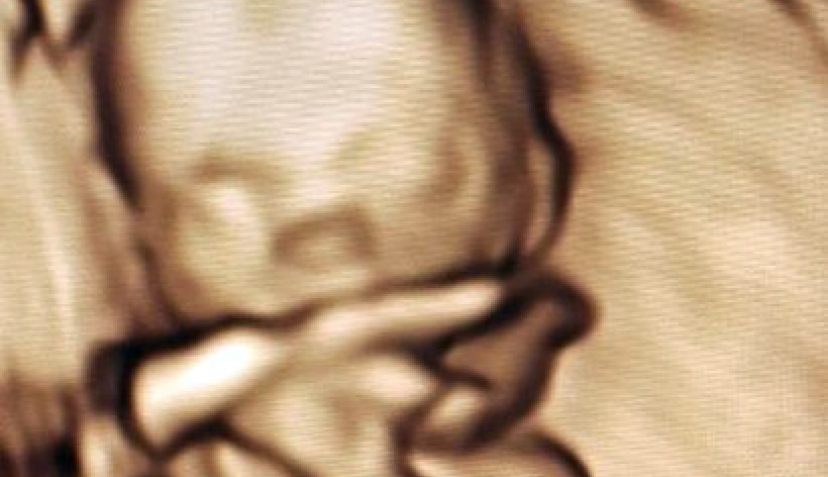

Zusätzlich bieten wir Ihnen seit 2018 die Möglichkeit, mit unseren hochauflösenden Ultraschallgeräten durch 3D- und 4D-Sonographie Ihr heranwachsendes Kind nicht nur in Umrissen, sondern auch räumlich zu erleben.

Bei der 4-D-Sonographie kommt die Dimension Zeit hinzu, wodurch am Ultraschallmonitor ein sich ständig aktualisiertes, dreidimensionales Bild entsteht, in dem sich Kindsbewegungen so gut wie ohne zeitliche Verzögerung darstellen lassen.